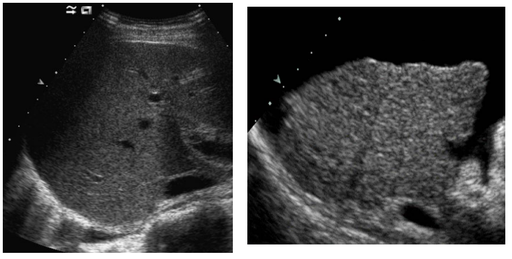

Foie : maladie chronique

DANSE E. - UCL

MASTER 1